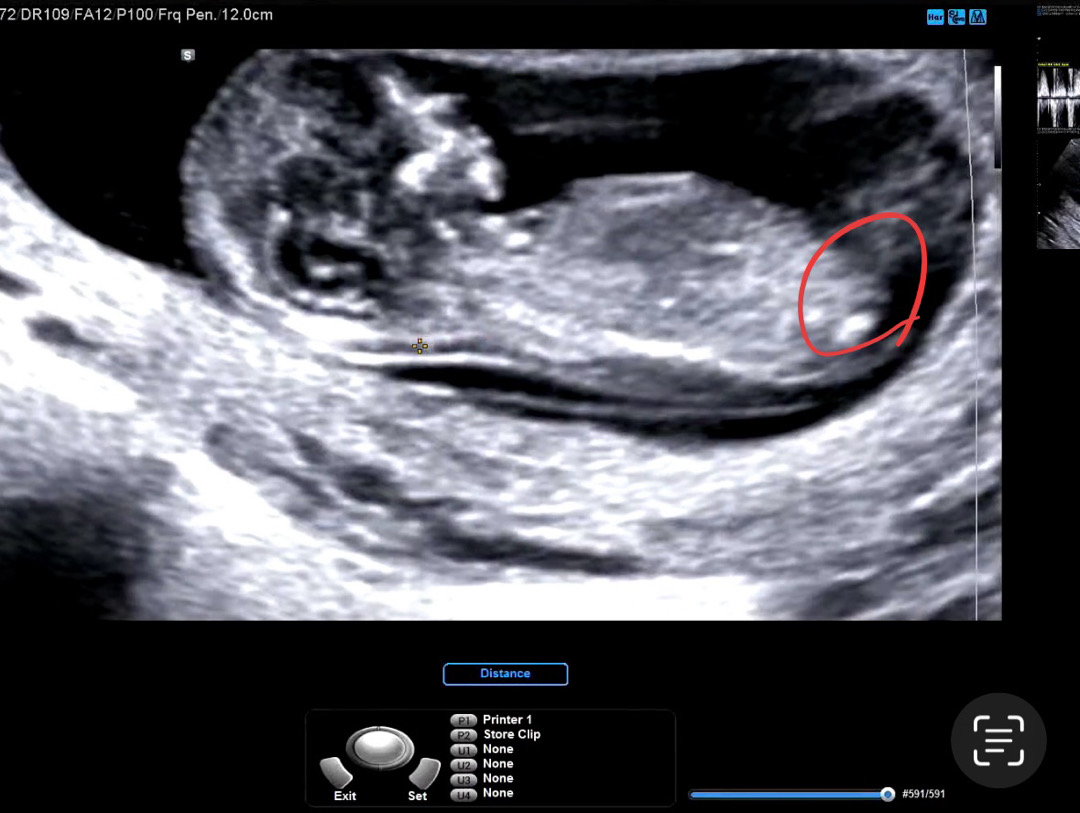

12주 각도법 질문드립니다.

초음파 찍고 왔는데 어떤 사진은 남아처럼 나오고 헷갈리네요ㅠ 사진 속 동그라미친 부분이 생식기 맞을까요?? 보시고 고견 부탁드립니다..